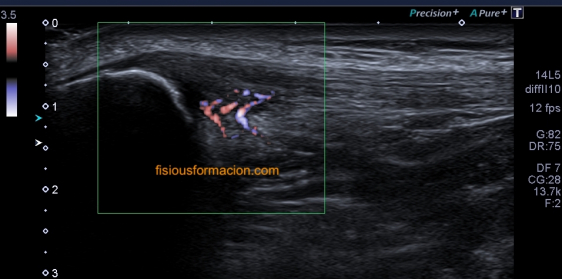

Una vez que tuve controlado el aspecto normal de músculo en la misma localización donde la paciente tenía el bulto, me dirigí a la región del bultoma y estudié la lesión, descrita con anterioridad, siguiendo el protocolo de actuación en caso de neoformaciones, control, medidas, doppler color y power y finalmente comparativa.

El estudio doppler arroja el hallazgo de un vaso importante que está alcanzando y nutriendo la región afectada. Puedes observar como es un vaso de alto flujo y de buen tamaño. No pude demostrar vascularización perimetral de la lesión.